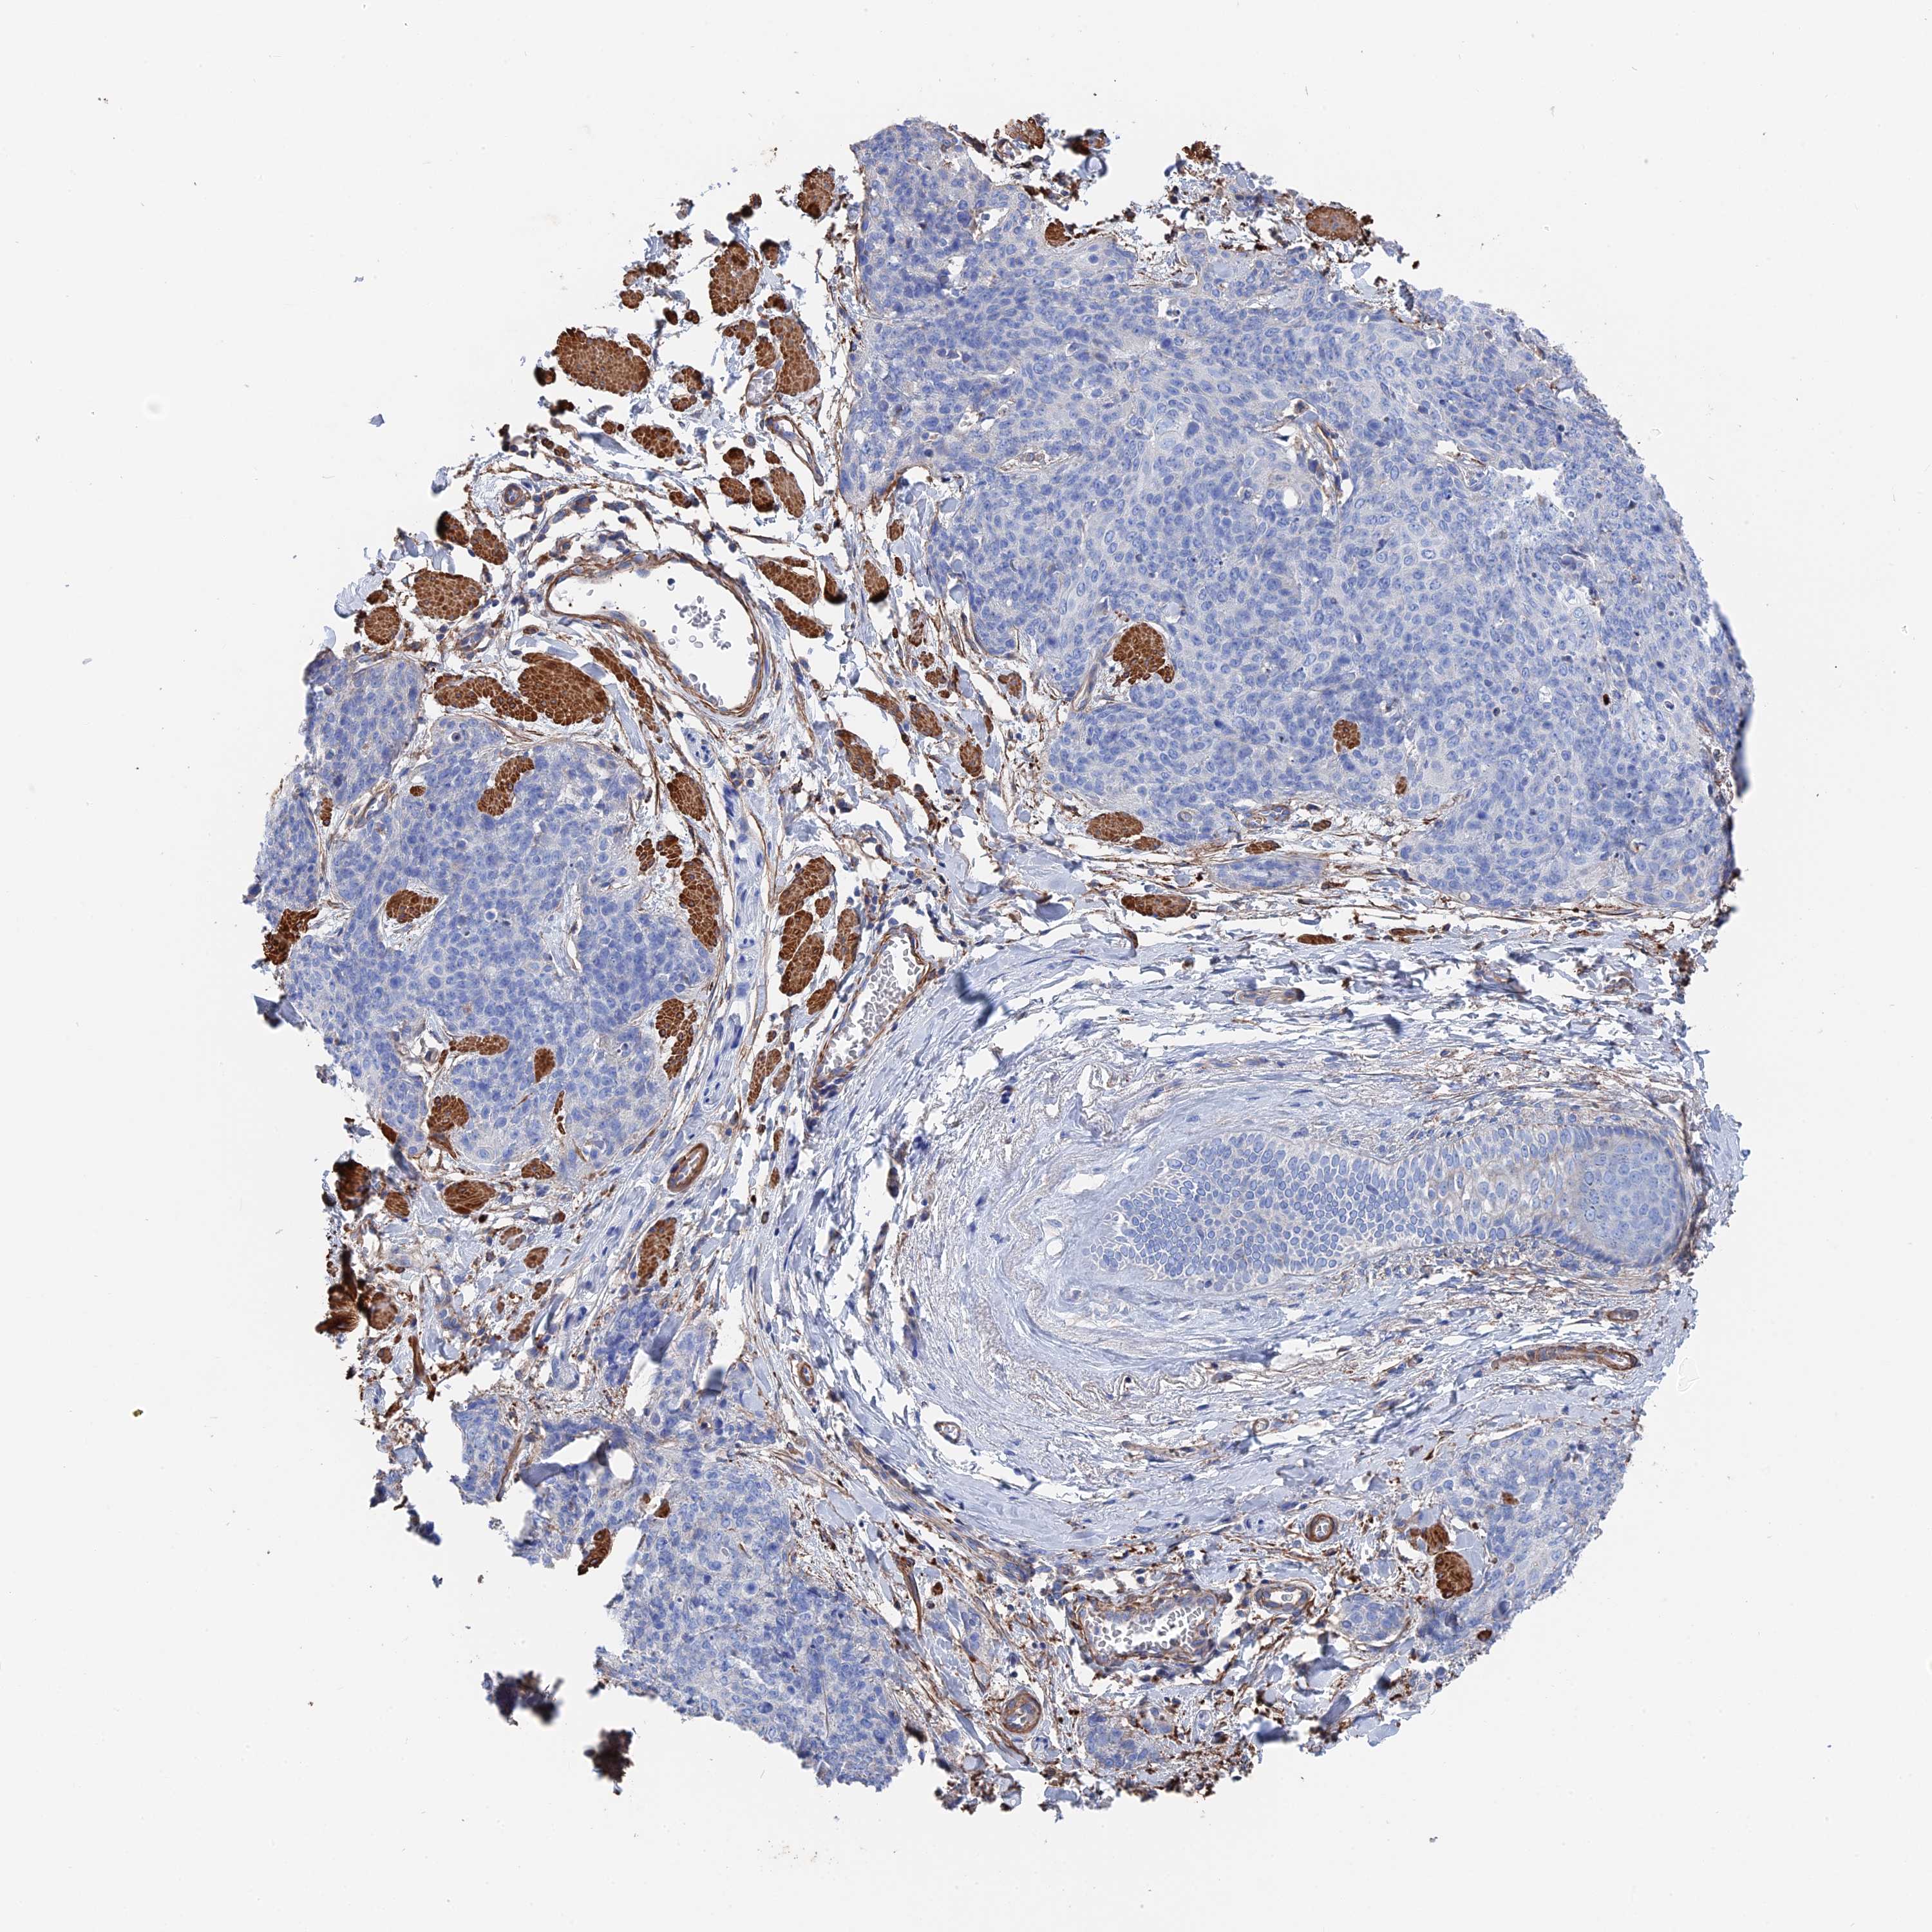

Antibody HPA040839

Staining

Medium

Intensity

Moderate

Quantity

75%-25%

Location

Cytoplasmic/membranous

Squamous cell carcinoma, metastatic, NOS

Squamous cell carcinoma, NOS